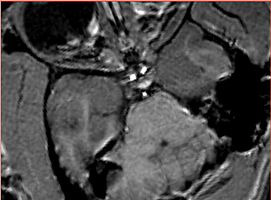

Valentino has structure not consistent with the normal anatomy Ron: this is likely a cyst.